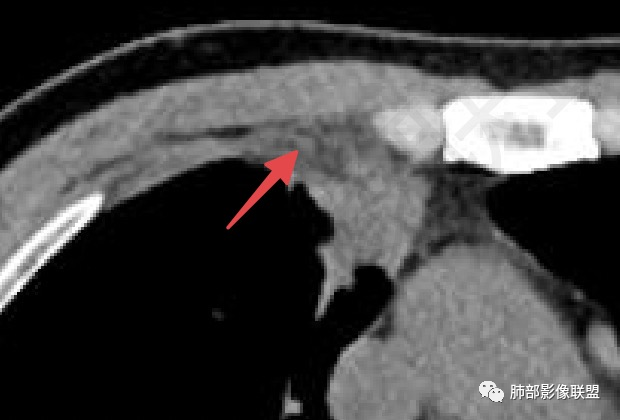

5

这里是软组织密度,纵隔内突入

我觉得这里可以怀疑是栽桩。